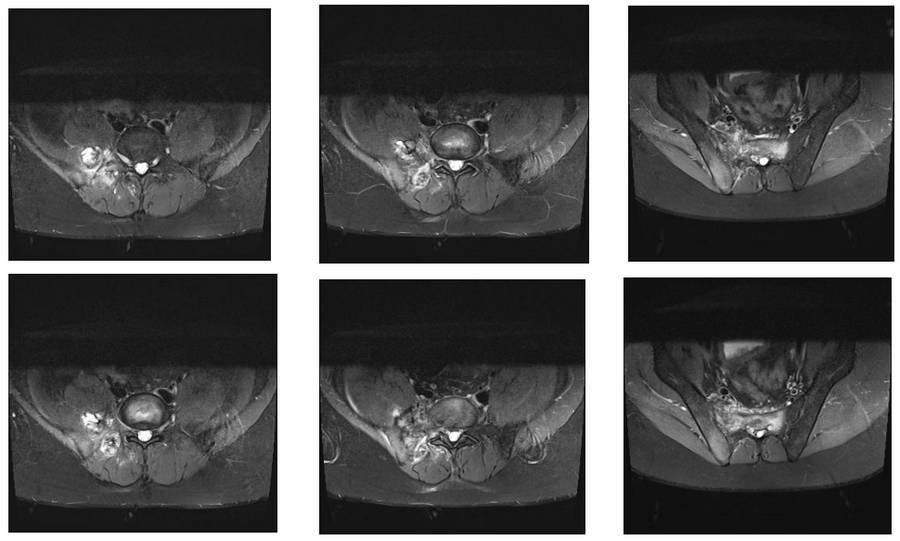

Ameliyat Öncesi: MR’da sağ iliak kanat posterior sakroiliak bölge üst kısım ve sakrumun tamamına yakınını kapsayan tümör dokusu ve çevreleyen ödem görülmekte